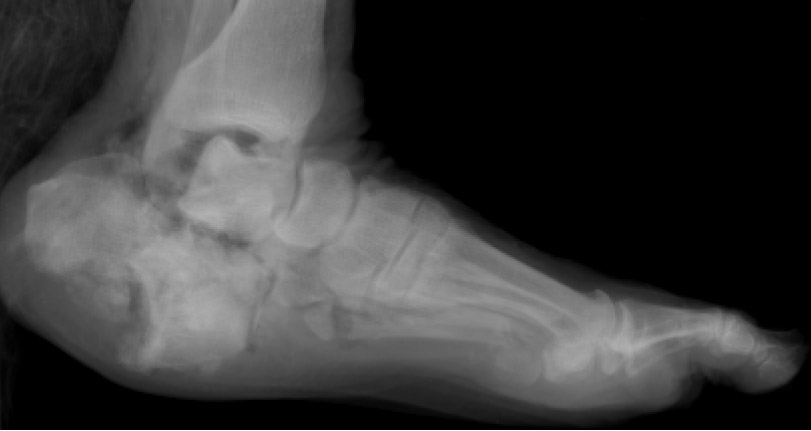

Pretest Radiographic Evaluations: The following pictures illustrate examples of the radiographic views utilized for the LEAP 99-2 study. These are examples of normal specimens taken before testing.

Picture 11 Lateral Foot

Picture 12 CT Femur